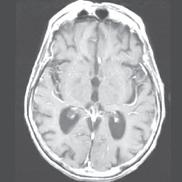

“When using standard MRI approaches, we are limited to brighter and darker shades of gray,” says MIITT co-director, Nicole Seiberlich, PhD, Research Professor of Cardiovascular Imaging and Associate Professor of Radiology. While radiologists are both skilled and experienced at reading and interpreting these images, introduction of a numerical measurement technique eliminates subjectivity, providing readers with specific data. “With our proprietary method, Magnetic Resonance Fingerprinting (MRF), radiologists can acquire quantitative data on multiple important properties simultaneously, which improves the accuracy of the diagnostic information. These quantitative tissue property maps include actual numbers that give experts reproducible and actionable results. It has been evaluated in brain, prostate, liver, cardiac, and musculoskeletal imaging.”

One of the many benefits of utilizing the MRF method as opposed to traditional MRI techniques is that it can be applied across vendors and machines to enable quantitative comparisons. “Before MRF, the shades of gray you received depended on all sorts of factors,” says Tom Griesler, MS, third year BME PhD candidate, whose research interests include MRF sequence design and optimization for brain and abdominal imaging. Results varied based on the series, settings, and manufacturer. Using MR Fingerprinting, numerical physical parameters enable comparison across time and space.

“We’re also developing something called quantitative T1rho mapping, an MRI-based measurement technique for contrast-free myocardial fibrosis detection,” says Sydney Kaplan, MS, 4th year BME PhD candidate. “This is part of my research where we’re trying to avoid administering gadolinium based contrast agents to patients who may have kidney disease. With standard scanning technology, we can’t see fibrosis on an MRI image. However, by using T1rho or an alternative method, Magnetization Transfer (MT), both of which are sensitive to macromolecules like collagen or proteins, we can see subtle changes in heart tissue.”